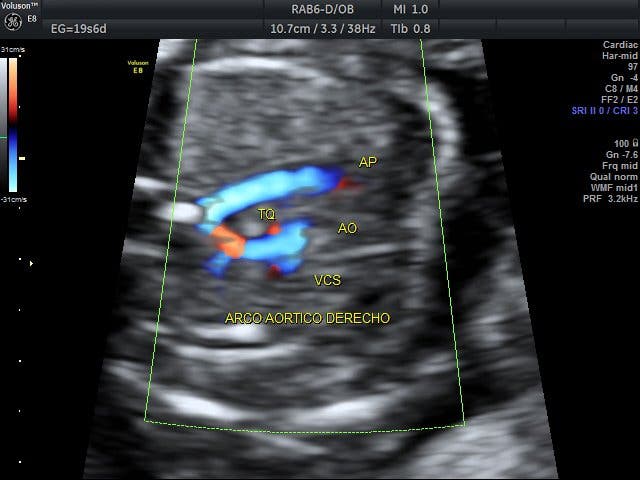

En noviembre pasado, participó en Valencia en el I Congreso Nacional de la Asociación Española de la Muerte Súbita (AEMS), donde explicó que fue a los 10 años cuando supo que padecía esta cardiopatía y que su corazón tenía una transposición de grandes vasos.

El «corazón al revés», la expresión coloquial utilizada por la propia Chacón para hablar de su cardiopatía congénita, denominada «transposición de grandes vasos», consiste en que el corazón está cambiado sobre su eje y las venas y arterias se conectan de forma incorrecta.

En el caso de Chacón, por sus propias declaraciones se puede también deducir que la transposición estaba asociada a un bloqueo auriculoventricular completo.